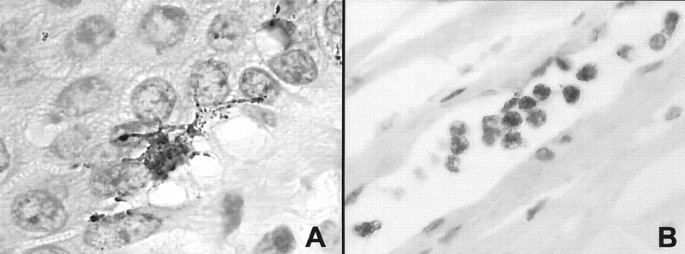

Results of PNL2 immunostainings on human non-neoplastic tissues are summarized in Table 1. PNL2 consistently gave a strong cytoplasmic staining of melanocytes on skin and oral mucosa sections and a moderate staining of granulocytes (Fig. 2). This staining was granular and cytoplasmic and highlighted dendritic prolongements of melanocytes. Except for melanocytes and granulocytes, no other cell was immunostained in the wide variety of normal human tissues tested. When the PNL2 supernatant was diluted, the melanocyte staining remained strong until high dilution were used (i.e., 1/50), whereas leukocyte staining disappeared at low supernatant dilution (i.e., 1/10).

PNL2 immunostaining of normal tissues is limited to melanocytes (A) and leukocytes (B): the staining of the skin melanocytes (A) is cytoplasmic and dendritic in a granular pattern. It remained strong up to a supernatant dilution of 1/50. The staining of leukocytes (B) is also cytoplasmic in a granular pattern but it rapidly disappears at low supernatant dilution (i.e., 1/10).